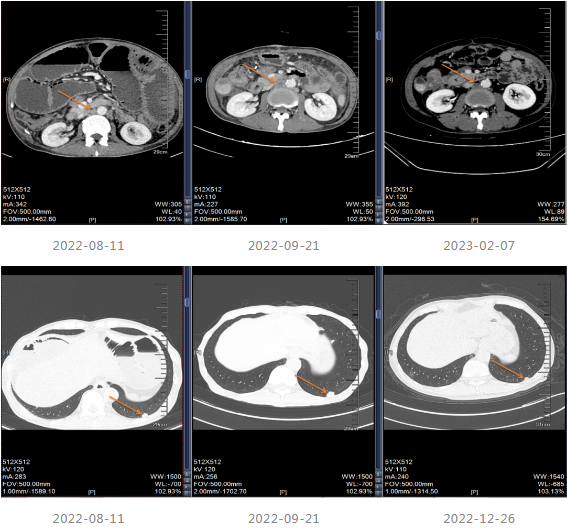

2021.06-01复查影像学提示肝胃间隙及腹膜后淋巴结较前增大,疗效评价PD。

2021-06-08至2021-12-11采用“贝伐珠单抗+Cap”治疗8个周期。

2021-12-15影像学复查提示疾病进展。

▌三线治疗

2021-12-20至2022-03-21更改化疗方案,采用“贝伐单抗+FOLFOX6方案”进行治疗。

2022-04至2022-07采用“贝伐珠单抗联合卡培他滨”维持治疗4周期,维持治疗期间患者渐感腹胀伴消瘦。

202-08出现肠梗阻,内科治疗效果不佳。

2022-08-29至武汉同济医院行小肠造瘘术。

▌四线治疗

患者出现肠梗阻,考虑病情PD,因此2022-10-06至今采用“斯鲁利单抗(200mg q3w)+呋喹替尼(4mg/d,口服,服3周停1周)”进行治疗,治疗过程中患者一般情况良好,体重增加。